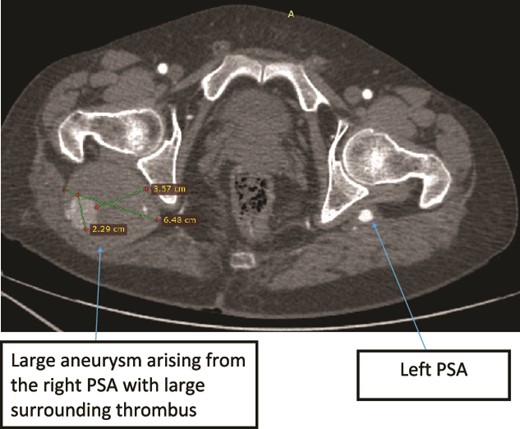

Case 2—axial images of LL CTA of the bilateral LL arteries at the level of the femoral head showing large bilateral PSAs and a large aneurysm with surrounding thrombus of the right PSA.

Case 2—sagittal images of LL CTA of the right LL arteries showing large aneurysm with surrounding thrombus with adjacent normal-sized PSA.